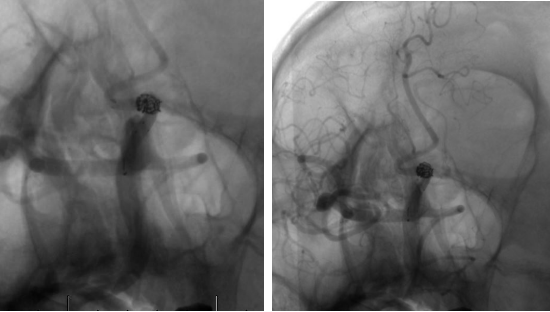

经右侧股动脉鞘,黑泥鳅导丝带领导引导管(Codman 6F Envoy DA)到达右侧颈内动脉岩段,微导丝(Synchro--14 0.014 in*200 cm)带领支架微导管(Excelsior SL--10)到达右侧大脑中动脉M2段,退出微导丝。微导丝带领弹簧圈微导管(Echelon10)到达右侧M1远端分叉处动脉瘤内,退出微导丝。经弹簧圈微导管填入弹簧圈(Codman 3 mm*4 cm)经支架微导管输送支架(Neuroform Atlas 3.0 mm*15 mm)并释放在M2段至M段中部,完全覆盖动脉瘤颈。继续经弹簧圈微导管依次填入弹簧圈数枚,间断造影确保右侧大脑中动脉及远端血流通畅。右侧颈内动脉造影确认:动脉瘤致密填塞,载瘤动脉通畅,手术结束。有侧股动脉穿刺处用血管封堵器封堵,并压迫器持续压迫。术后患者麻醉清醒,拔除气管插管,呼唤应答,对答切题,言语清楚,四肢肌力肌张力正常。安返病房。

患者在全麻下、多参数监护仪监测下行前交通动脉瘤经右侧颈内动脉支架辅助下栓塞术。全麻后,常规消毒销巾,采用改良seldinger技术穿刺右侧股动脉或功,置入6F动脉鞘。黑泥鳅导丝及多功能导管带领6F MPD导管达到右侧颈内动脉岩段,行造影见∶前交通动脉瘤,瘤体3.5 mm*5.1 mm。在路图引导下,徵导丝(Synchro 0.014 in*200 cm)带领弹支架微导管(SL-10)到右侧大脑前动脉A2段,退出微导丝。微导丝(Synchro 0.014 in*200 cm)带领弹簧圈微导管(eV3 Echelon-10)到达前交通动脉瘤体内,退出微导丝。经弹簧圈微导管填入首枚弹簧圈(Codman COMPLEX XTRASOFT3 mm*6 cm)成篮良好,在路图引导下在支架管内输送支架(Neuroform Atlas 3.0 mm*21 mm)并释放完全覆盖动脉瘤颈,造影可见支架打开良好解脱首枚弹备圈,沿弹簧圈导管继续填入弹簧圈(可见护理记录单)间断造影确保双侧大脑前动脉血流通畅。右侧颈内动脉造影确认∶前交通动脉瘤填塞致密,双侧大应前动脉血流通畅。手术结束。右侧股动脉鞘处用血管封堵器(Coxrds Exoseal 6F)封堵,并压迫器持续压迫。木后患者清醒。

Neuroform Atlas支架系统是Neroform支架的新一代产品,其改进后的设计可以使支架经更细的微导管输送(Atlas可以通过0.0165 inch内径的微导管输送,而以前的支架产品一般只能通过0.027 inch内径的较粗微导管输送)。较前代Neuroform支架相比,Atlas支架在操作上易输送,通过性强,易定位、释放,释放时张力小,无明显上下移位,贴壁性好,Atlas支架具有更佳的“脚手架”作用。